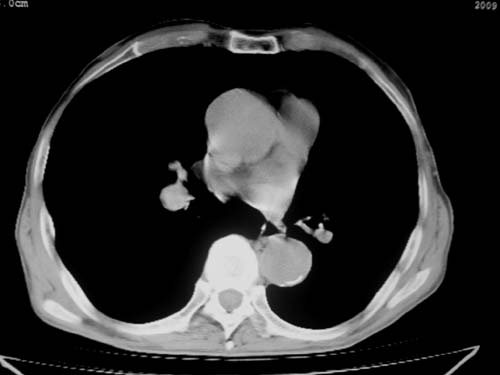

标题: CT19736:男,76岁,咳嗽,胸痛 [打印本页]

标题: CT19736:男,76岁,咳嗽,胸痛

支持左上肺周围型肺癌性并空洞形成伴胸椎转移。

支持 左上肺周围型肺癌性并癌性空洞形成伴胸椎转移。

考虑癌性空洞并胸椎转移。

空洞内壁有多发结节,支持癌性空洞。